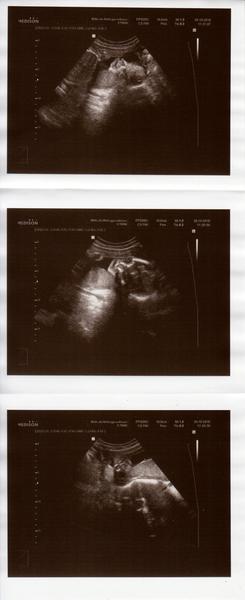

@krisatko @halasovci007 holky, muzeme byt rady, ze se nam mimca drzi hlavickou dole, snad jim to teda vydrzi az do konce 😊

@krisatko mi mudra rikala, ze to zalezi, kolik tam bude mit mista, pokud pak, az poporoste bude se citit ztisnene, muze se otocit, ze je jeste brzy delat zavery. Tak doufam, ze tam bude hlavickou dole spokojeny 😊 a hlavne at ma dost dlouhy pupecnik, aby nedelal fory pak pri druhe dobe

@priefi jj taky jsme hlavou dole teda doufsm,ze se to nezmeni,ale dr. rikal,ze uz je velka,ze by otocit uz nemela cela..

Ze radici deti budou na svete hodne tak to ja budu mit pohodicku 😂😂 mala radi to je neskutecny !! Jen se bojim zda se fakt neotocila ptz cejtim pohyby i dole a n3vim zda by takovy pecky davala i rucickama 😟@krisatko a neni to strasidlo jak manzel rika!!